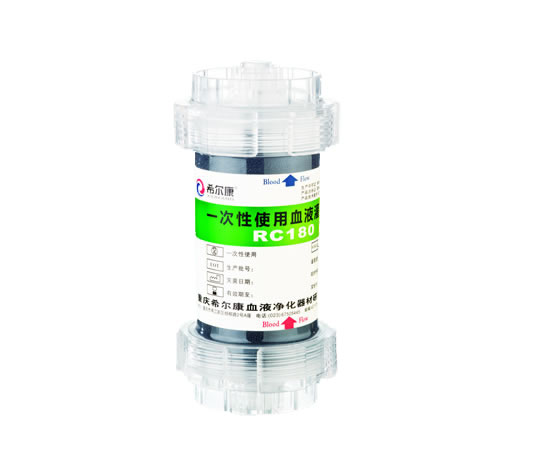

树脂炭血液灌流器-RC180

RC系列

树脂炭血液灌流器-RC180

快清®树脂炭血液灌流器